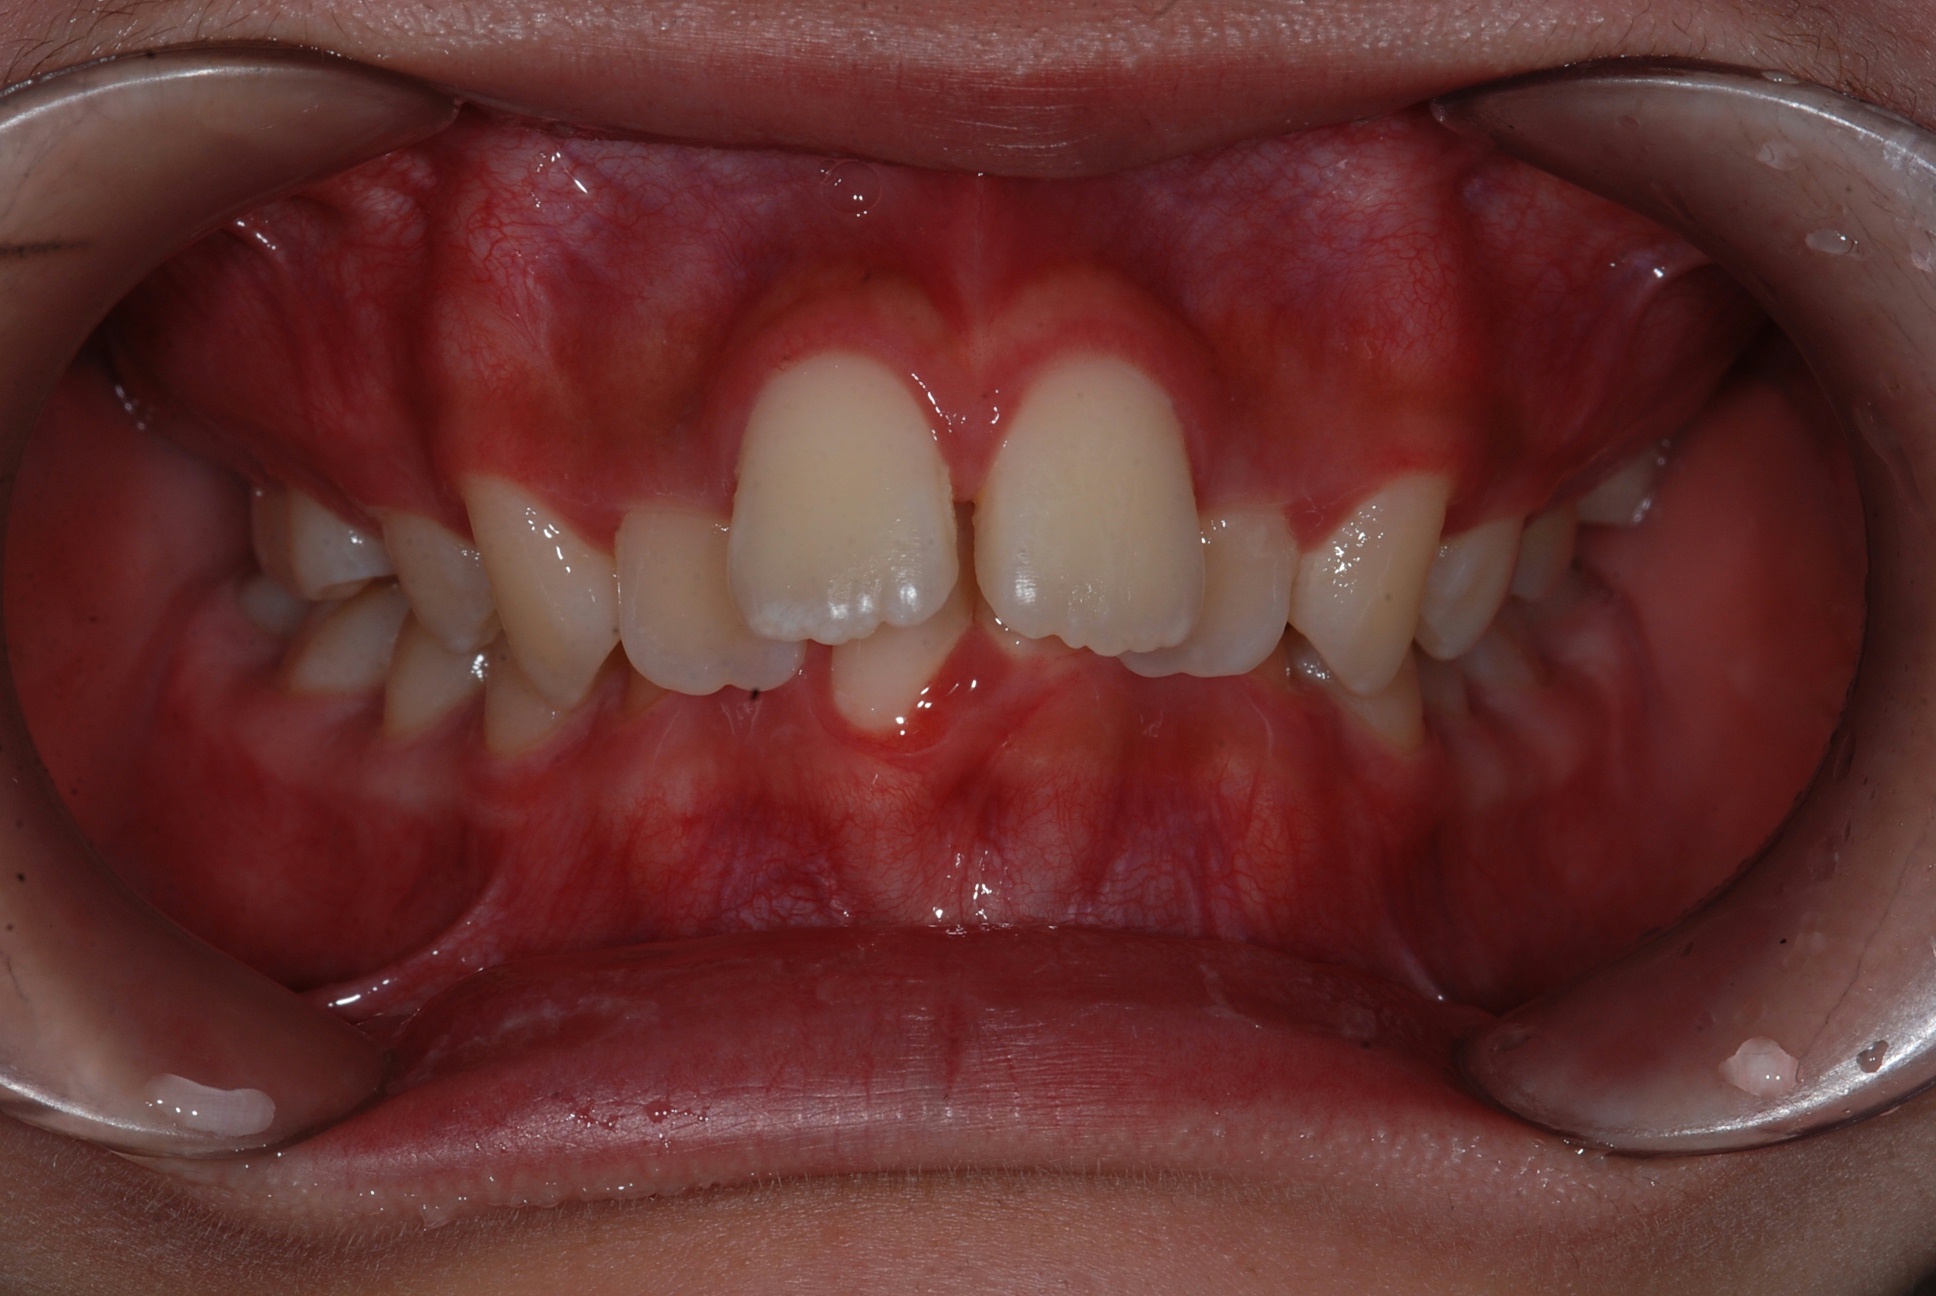

치료 전 사진입니다.